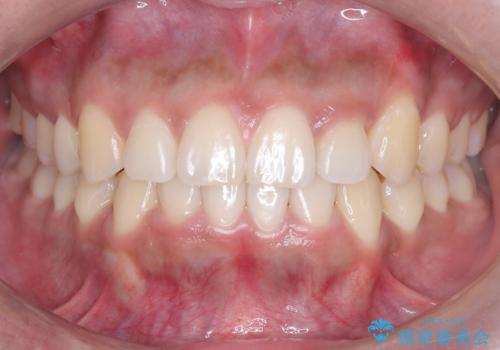

【非抜歯】インビザラインで正しい噛み合わせを

目立たない装置でデコボコを改善 ハーフリンガルによる矯正治療

前歯のガタつきを治したい 翼状捻転マウスピース矯正

八重歯とクロスバイト:インビザライン治療

非抜歯で短期間!ワイヤー矯正で理想の歯並びを実現